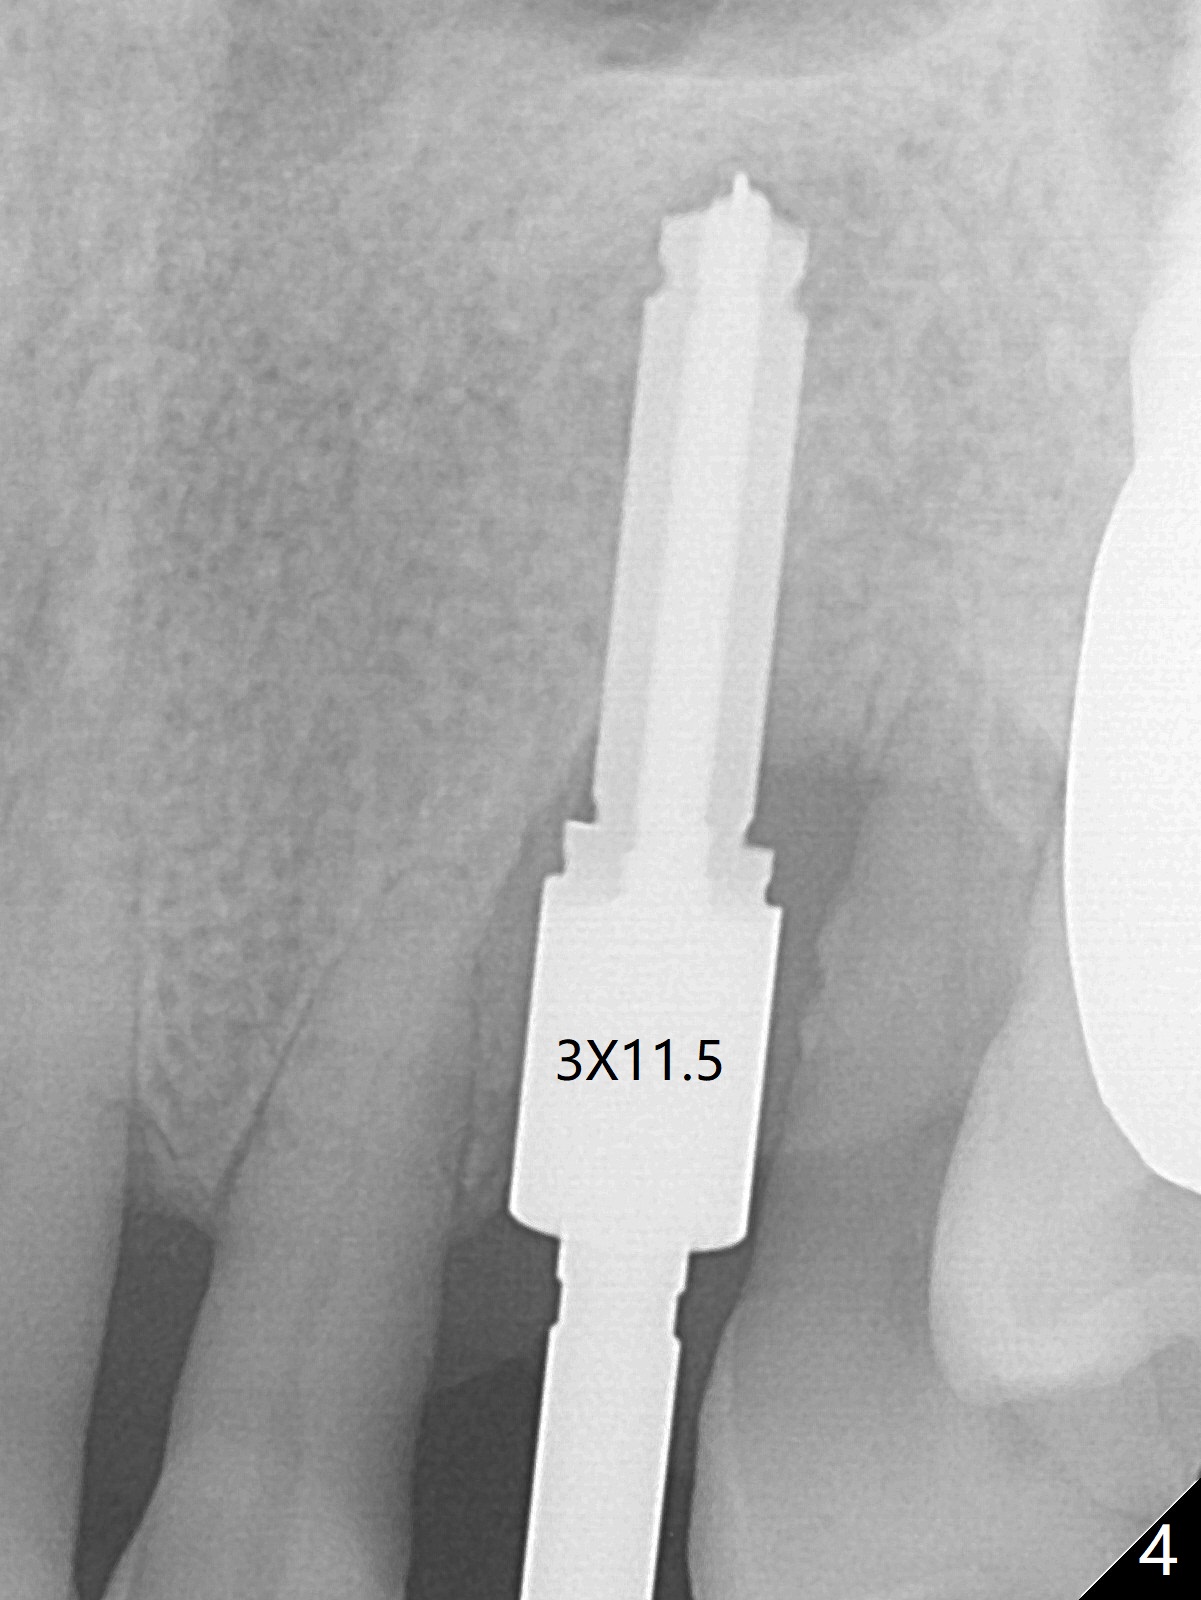

A 62-year-old man with generalized chronic periodontitis returns with chief complaint of loose tooth at #11 (Fig.1). Although a buccal fistula (Fig.1 <) is closer to #12 than to #11, percussion is more severe at #11 than 12. The buccal plate of #11 is missing, but it is possible to place a narrow immediate implant because of the wide alveolus (Fig.2). Since the gingiva is ~ 10 mm long, a mill abutment is to be used (Fig.3,5). In fact the fistula communicates with #11 extraction socket. After debridement, osteotomy is initiated (Fig.4) for a 3.8x10 mm implant ~ 35 Ncm, followed by seating a 4.5x2 mm mill abutment (Fig.5). Abundant sticky bone is placed in the remaining socket (for buccal plate reconstruction) and against the root surface of the neighboring teeth (Fig. 6 * (#10,12)). Finally 2 pieces of PRF membranes are utilized to facilitate repair of the buccal soft tissue defect (Fig.7 *). The root prominence of the canine seems to be maintained by the bone graft (Fig.8 C). Acrylic dressing holding the PRF membranes in place remains in situ with the healthy gingiva buccal (Fig.9) and palatal (Fig.10) 11 days postop. Note the acrylic locking into the undercuts of the neighboring teeth (*). 经过一段摸索发现离心每分钟1500转5分钟后,抽取上清液,接着再离心10分钟剩余上清液就形成血小板块,压制后便是血小板膜,后者似乎有助于软组织愈合,而上清液用来制备骨块,帮助硬组织生长。利用这个原则讨论以下病例治疗。The gingival margin gains ~ 5 mm 6 weeks postop when the acrylic dressing is removed (Fig.11,12 (<: previous one), as compared to Fig.7,8). 治疗结束时尖牙牙龈缘高于第一双尖牙(图七,八),六个星期后,尖牙牙龈缘却低于双尖牙(图十一,十二(箭头:原始牙龈缘))。术后2.5,4.5月基台周围牙龈似乎能与钛合金附着,防止细菌进入深部植体(图十三,十四)。临时牙冠脱落多次,可能与mill abutment太光滑有关,所以颊侧,舌侧磨成平面(图十四)。取模时好像不必取出基台清洗(仿佛没有炎症),原位用树脂延长基台。术后5个月CT显示颊侧骨板再生(图十六-十八)。取模时并没有用树脂加长基台;粘固时,牙冠颜色理想,但是照片中并不是如此(图十九,二十),颊侧骨板没有塌陷。术后11个月基台颊侧骨板没有萎缩(图二十一:B);3d图像:骨壁完全形成(图十六对比:部分形成)。密度也增高(图二十二:B),与术后五个月比较(图十七)。术后十一个月,粘固后五个月角化龈存在(图二十三),牙冠颈部有金属颜色透出,是因为二段式基台太粗了(最细4.5毫米),可以请实验室在牙冠内部涂opaque material而减轻。